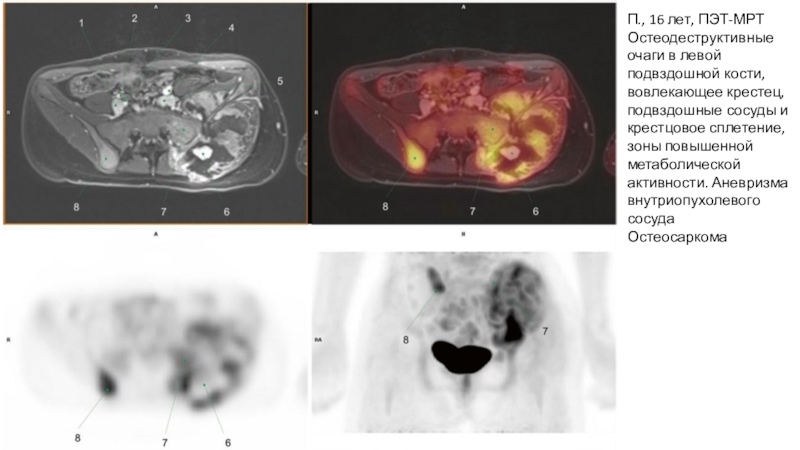

Слайд 19П., 16 лет, ПЭТ-МРТ

Остеодеструктивные очаги в левой подвздошной кости, вовлекающее

крестец, подвздошные сосуды и крестцовое сплетение, зоны повышенной метаболической активности.

Аневризма внутриопухолевого сосуда

Остеосаркома

П., 16 лет, ПЭТ-МРТОстеодеструктивные очаги в левой подвздошной кости, вовлекающее крестец, подвздошные сосуды и крестцовое сплетение, зоны